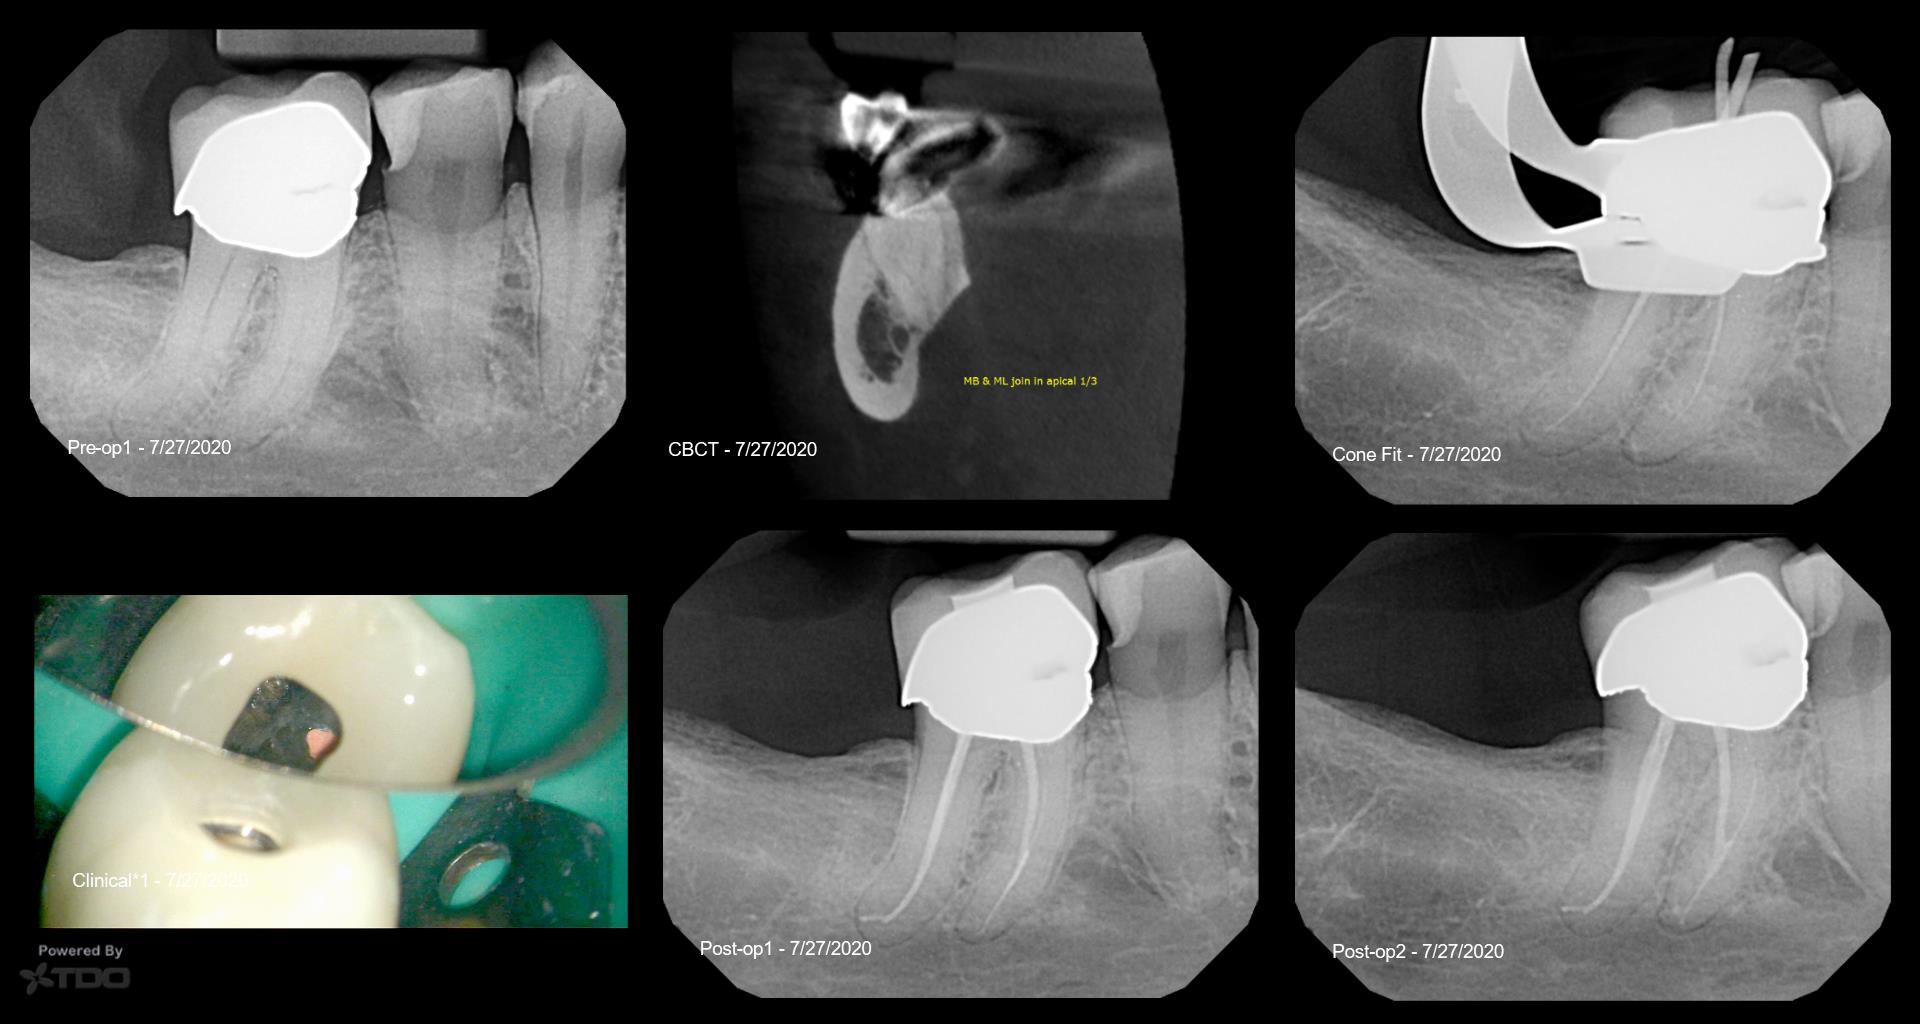

New to TDO-giving the publishing feature a shot. Vital tooth #30 (46) from yesterday. Lingering pain to hot. Dx: SIP/SAP. Class V amalgam resulted in an obstructed/calcified MB & DB orifices (only accessed ML & DL aspect of oval D canal). Mesials joined in apical third. 20v06 instrumentation 1.5mm short of M & D POEs. Gentlewave Procedure completed. BC HiFlow Sealer tracked coronally into MB upon slight downpack during obturation.

Great to see you utilizing TDO for publishing. Your detailed case description showcases your expertise in endodontics. Impressive handling of a challenging MB obstruction.